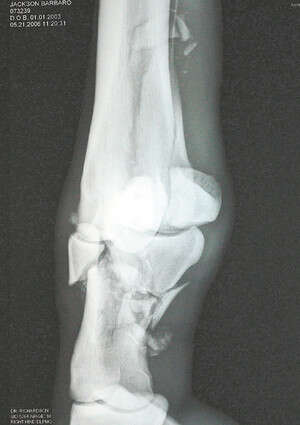

אלא שאז קרא האסון: 130 מטרים בתוך המירוץ עיקם לפתע ברברו את הקרסול הימני האחורי. אדגר פראדו, הג'וקי המיומן, הרגיש שיש תקלה ומיד שחרר את הלחץ מהסוס כדי שפציעתו הראשונית לא תחמיר.

ומה עם ברברו? ובכן 23 הברגים שהוכנסו לרגלו של ברברו לצורך שיקומה הבהירו בברור כי קריירת המירוצים שלו מתה בדמי ימיה. אולם כשמדובר בסוסי מירוץ, ניצחון הוא רק צד אחד של הסיפור. ברברו אומנם שווה 50 מיליון דולר בריא, אבל גם על ערש דוואי הגנטיקה שלו שווה הרבה כסף. המון כסף.

לפני כשבוע הגיעו חדשות רעות. "יש לו לא מעט סיבוכים בימים האחרונים. החשש הגדול שלנו הוא מכך שהתפתחה דלקת ברקמת החיבור שהפרסה מחוברת אליה", אמר ", אמר ד"ר דין ריצ'ארדסון לאומה אמריקאית מודאגת, אך הציע תקווה כשאמר כי כבר היו מקרים (מועטים) בהם סוסים שרדו מצב דומה.